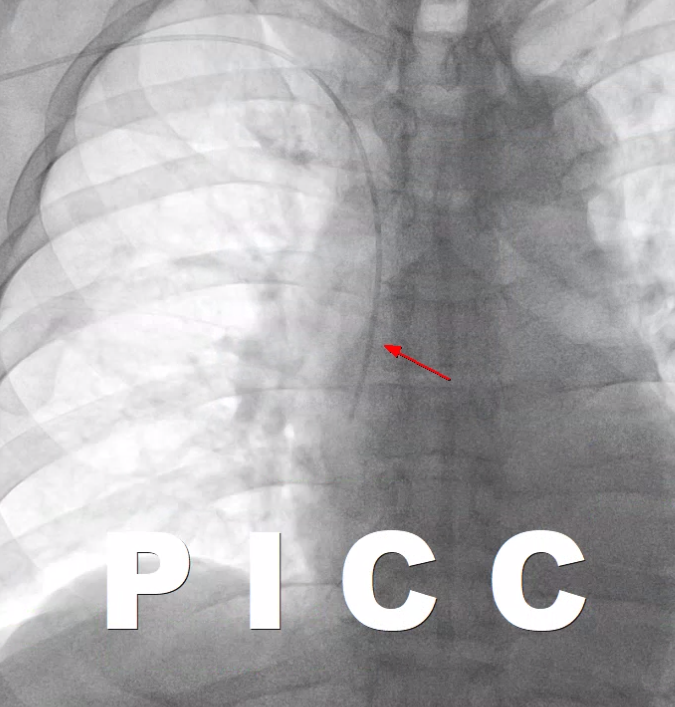

그 와이어를 따라서 정맥관을 삽입합니다. 정맥관의 끝 부분은 보통은 상대정맥과 우심방 사이에 놓습니다.